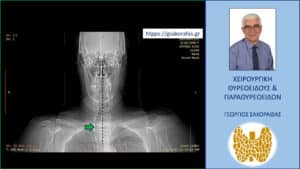

Τοπόγραμμα αξονικής τομογραφίας. Εμφανής η απώθηση της τραχείας (πράσινο βέλος) προς τα δεξιά της μέσης γραμμής (κάθετη μαύρη διακεκομμένη γραμμή)